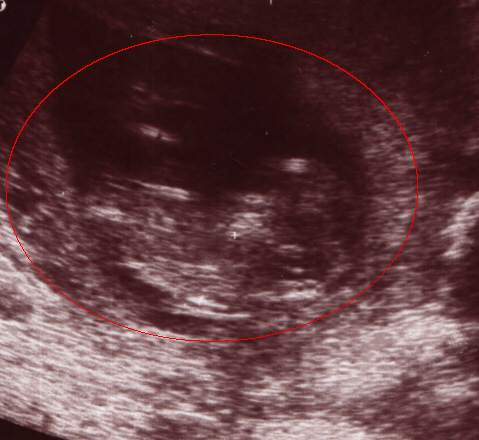

11 Wochen

Hier ist Ivo circa 5cm groß. Sein Köpfchen befindet sich hier auf dem Bild rechts.